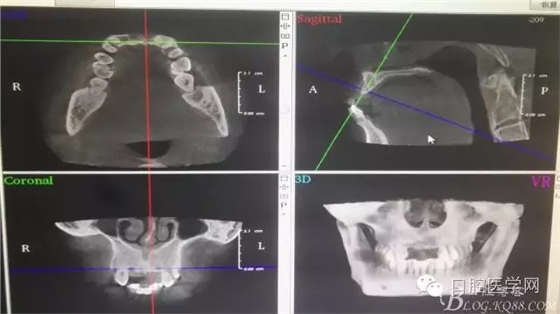

為他院轉(zhuǎn)診患者。男,無吸煙史,前牙因齲壞治療后,外力折斷導(dǎo)致拔除。現(xiàn)拔除該牙后兩個多月。 左上區(qū)域骨寬度不足,計劃植入種植體同期GBR。

左上區(qū)域骨寬度不足,計劃植入種植體同期GBR。